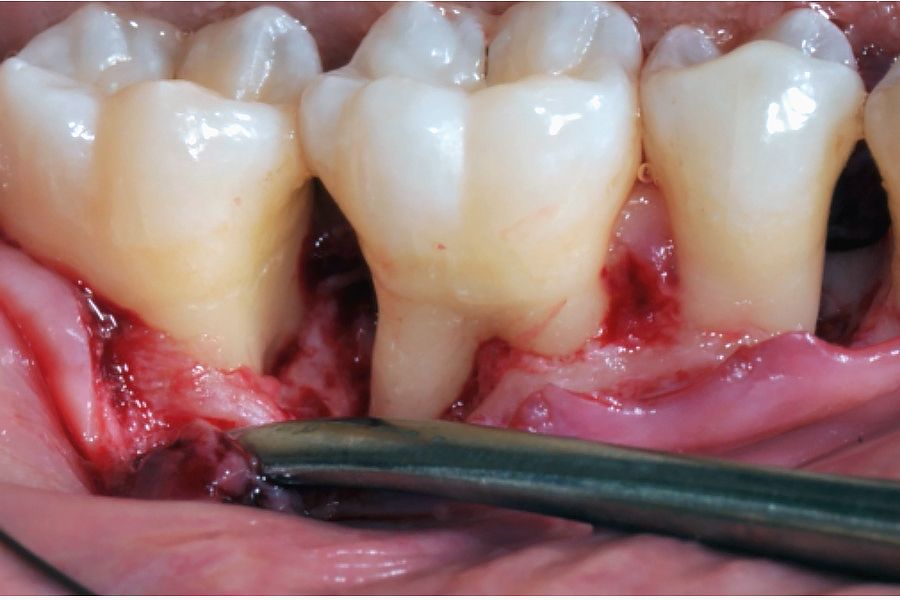

Nach Lokalanästhesie wurde ein Mukoperiostlappen abgehoben, der sich distal von Regio 43 bis mesial nach Regio 47 erstreckte. Das suprakrestale Weichgewebe über den keilförmigen Defekten wurde mit der erweiterten Technik zur Papillenerhaltung zwischen Regio 47 und 46 und mit der vereinfachten Technik zur Papillenerhaltung zwischen Regio 45 und 44 erhalten (Abb. 4-5). Der Lappen wurde nach einem Split-Full-Split-Ansatz abgehoben. Die chirurgischen Papillen wurden als Spaltlappen, der mittlere Bereich des Lappens dagegen als Volllappen abpräpariert, bis die Knochendefekte vollständig freigelegt waren. Der linguale Lappen wurde zusammen mit dem suprakrestalen Weichgewebe im Interdentalbereich als Volllappen abgehoben. Auf die Lappenhebung folgte ein Debridement: Beide Knochendefekte wurden degranuliert und die Wurzeloberflächen mit Ultraschall und manuellen Instrumenten geglättet. Der infraalveoläre Defekt in Regio 46 wurde im koronalsten Anteil als zweiwandiger Defekt (fehlende vestibuläre Lamelle) eingestuft, welcher im apikalen Bereich in einen dreiwandigen Defekt überging. Der infraalveoläre Defekt in Regio 45 wurde im koronalsten Anteil als einwandiger Defekt eingestuft, während im apikalen Bereich ein dreiwandiger Defekt vorlag (Abb. 6-7). Die Wurzeloberflächen wurden 2 Minuten lang mit 24%igem EDTA-Gel konditioniert, um die bei der Wurzelglättung entstandene Schmierschicht (Smear Layer) zu entfernen. Nach dem Spülen mit Kochsalzlösung wurde Emdogain® auf die freiliegende Wurzeloberfläche und in die Defekte appliziert (Abb. 8-9). Die anatomischen Papillen zwischen Regio 43 und 44 und zwischen Regio 45 und 46 wurden deepithelisiert, und der bukkale Gewebelappen wurde nach koronal verschoben, um die chirurgischen Papillen mit Einzelknopfnähten am Bindegewebe der anatomischen Papillen zu vernähen. Das im Bereich der infraalveolären Defekte (Regio 44 – 45 und 46 – 47) erhaltene interdentale Weichgewebe wurde mit Einzelknopfnähten (Vicryl 6-0) primär vernäht (Abb. 10-11). Der Patient wurde angewiesen, den behandelten Bereich nicht zu putzen. Eine Plaquekontrolle wurde 15 Tage lang dreimal täglich mit 0,12%iger Chlorhexidin-Lösung durchgeführt. Zusammen mit einer entzündungshemmenden Therapie (Ibuprofen 600 mg zweimal täglich für 2 Tage und anschliessend nach Bedarf) wurde eine systemische Antibiotikatherapie (Amoxillin 1 g zweimal täglich für 7 Tage) verschrieben. Die Nähte wurden nach 15 Tagen entfernt (Abb. 12-13).